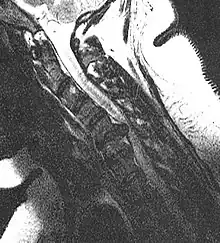

MRI scan of cervical disc herniation between C5 and C6 vertebrae.

MRI scan of cervical disc herniation between C6 and C7 vertebrae

Cervical disc herniations occur in the neck, most often between the fifth and sixth (C5–6) and the sixth and seventh (C6–7) cervical vertebral bodies. There is an increased susceptibility amongst older (60+) patients to herniations higher in the neck, especially at C3–4.[22] Symptoms of cervical herniations may be felt in the back of the skull, the neck, shoulder girdle, scapula, arm, and hand.[23] The nerves of the cervical plexus and brachial plexus can be affected.[24]

- Magnetic resonance imaging is the gold standard study for confirming a suspected LDH. With a diagnostic accuracy of 97%, it is the most sensitive study to visualize a herniated disc due to its significant ability in soft tissue visualization. MRI also has higher inter-observer reliability than other imaging modalities. It suggests disc herniation when it shows an increased T2-weighted signal at the posterior 10% of the disc. Degenerative disc diseases have shown a correlation with Modic type 1 changes. When evaluating for postoperative lumbar radiculopathies, the recommendation is that the MRI is performed with contrast unless otherwise contraindicated. MRI is more effective than CT in distinguishing inflammatory, malignant, or inflammatory etiologies of LDH. It is indicated relatively early in the course of evaluation (<8 weeks) when the patient presents with relative indications like significant pain, neurological motor deficits, and cauda equina syndrome. Diffusion tensor imaging is a type of MRI sequence used for detecting microstructural changes in the nerve root. It may be beneficial in understanding the changes that occur after herniated lumbar disc compresses a nerve root, and might help in differentiating the patients that need surgical intervention. In patients with a high suspicion of radiculopathy due to lumbar disc herniation, yet the MRI is equivocal or negative, nerve conduction studies are indicated.[43] T2-weighted images allow for clear visualization of protruded disc material in the spinal canal.